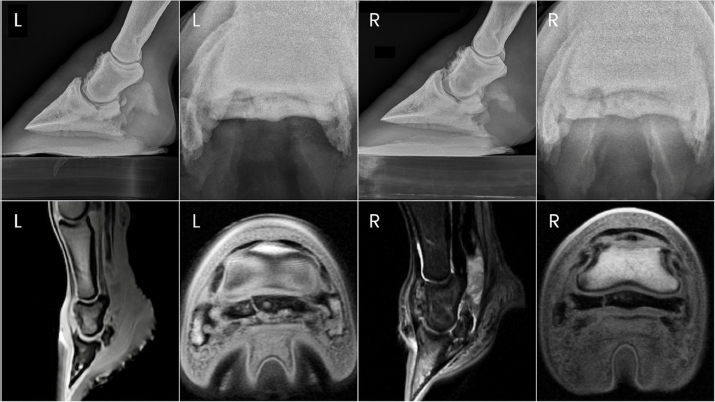

Fig. 1. Preoperative radiographs of the digits of horse 1.

Two years after donation, the gelding had progressed to displaying a grade 4/5 left forelimb lameness. This lameness was eliminated with diagnostic anesthesia of the left palmar digital nerves at the level of the proximal interphalangeal joint and replaced by a grade 4/5 right forelimb lameness. The right forelimb lameness was then eliminated with diagnostic anesthesia of the right palmar digital nerves in a similar fashion. PDN was performed as a salvage procedure to maintain pasture soundness. Abnormalities noted on the immediate preoperative radiographs included severe navicular bone degeneration bilaterally, osteoarthritis of the proximal and DIPJs bilaterally, and a focal area of mineralization in the area of the left DDF tendon just proximal to the navicular bone (Fig. 1).